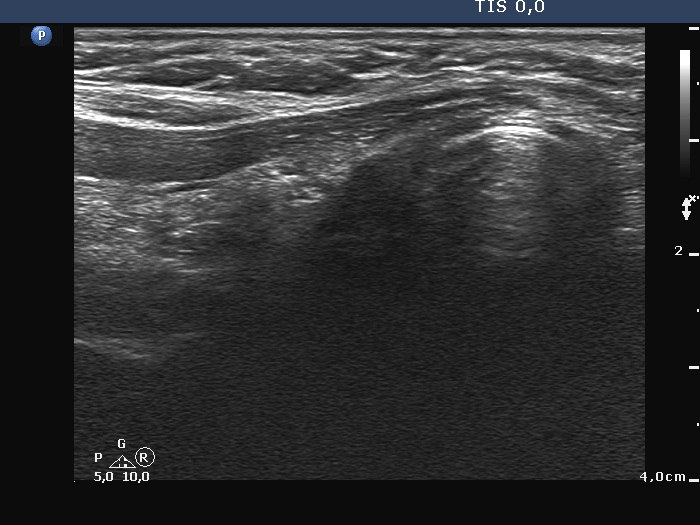

Ultrasonography. There was no thyroid tissue in the thyroid beds. Approximately 7 cm above the thyroid in the left side of the neck there were multiple, moderately hypoechoic lesions which presented tiny cystic areas. They had vascularity but did not have capsule.